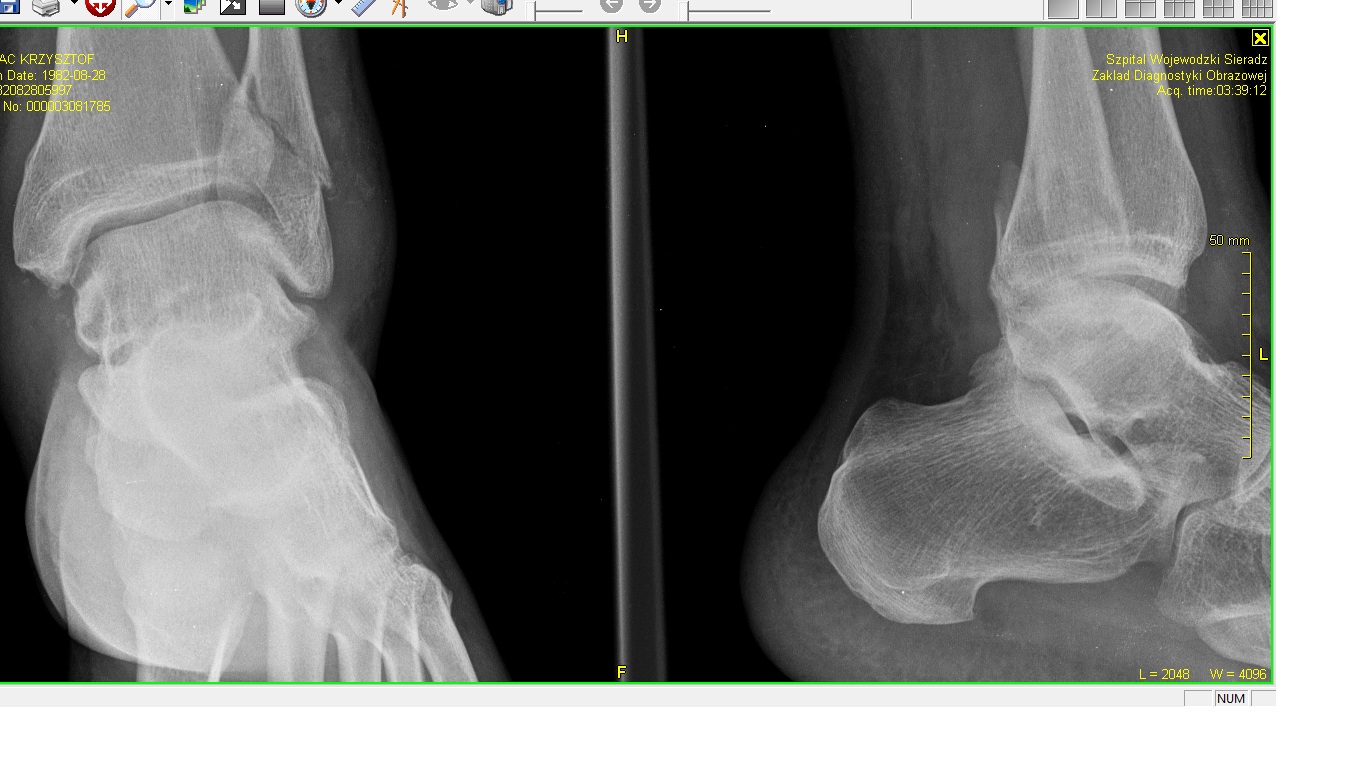

Złamanie kostki kości strzałkowej !!!

Złamałem kostkę kości strzałkowej, wpakowali mnie w gips ... Wygląda mi to na złamanie z przemieszczeniem, ale może mi się tylko wydaje.

Niech mi ktoś powie, czy to dobrze i jak sprawa wygląda z całą linią leczenia takiego złamania.

Załączam zdjęcie RTG.